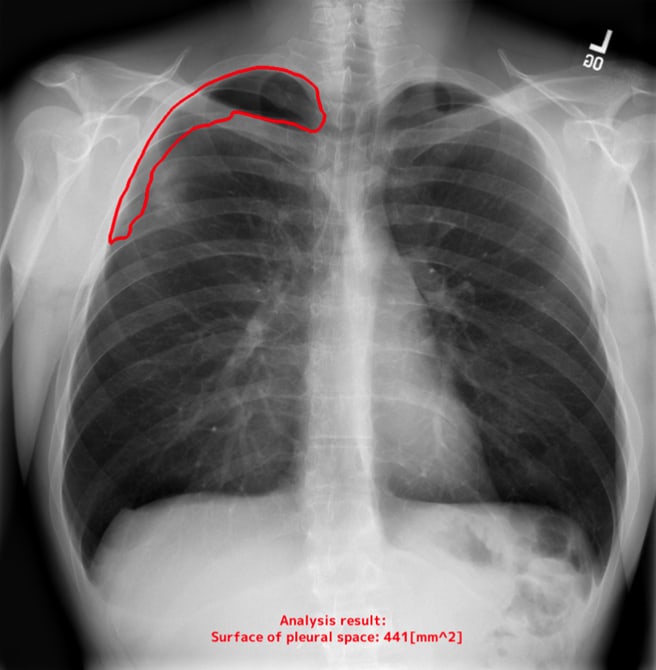

計測の自動化による日常業務の負荷軽減

EIRLが胸部X線画像上のランドマークを認識し、自動で計測。計測のばらつきを抑えながら、日常業務の負担を大幅に軽減します。

自動計測機能